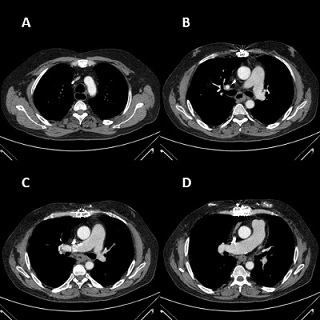

A 58-year-old male patient who underwent bilateral lung transplant due to pulmonary hypertension 6 years earlier, and a past personal history of type 2 diabetes, atrial flutter, sleep apnea syndrome and steatohepatitis, and immunosuppressive therapy with tacrolimus, mycophenolate and prednisone. The patient presented a 4-month history of dysphagia with mild weight loss. Endoscopy revealed an esophageal tumor in middle thoracic esophagus (Figure 1) with a histological diagnosis of SCEC, staged as TxN1M0 by CT-scan and CT-Positron Emission Tomography (PET) (Figure 2). After multidisciplinary team meeting, the patient received 4 weekly cycles of neoadjuvant chemotherapy with carboplatin AUC 2 and Paclitaxel 60mg/m2, without radiotherapy because of lung radiotoxicity risk. After finishing neoadjuvant treatment, a new PET was performed showing tumor progression but without tracheal or bronchial infiltration. The patient was proposed for surgery assuming high risk of medical and surgical complications. Laparoscopic-assisted transhiatal esophagectomy was performed, with a gastric tubulization using Akiyama method, hand-sew cervical anastomosis, and a jejunostomy tube was placed for enteral feeding. Thoracoscopic access was discarded because of bilateral lung transplant past history. No lymphadenectomy was performed for subcarinal or tracheobronchial nodes to avoid the risk of bronchial isquemia.

Figure 2: (A, B, C, D) Preoperative chest computed tomography.Figure 2: (A, B, C, D) Preoperative chest computed tomography.